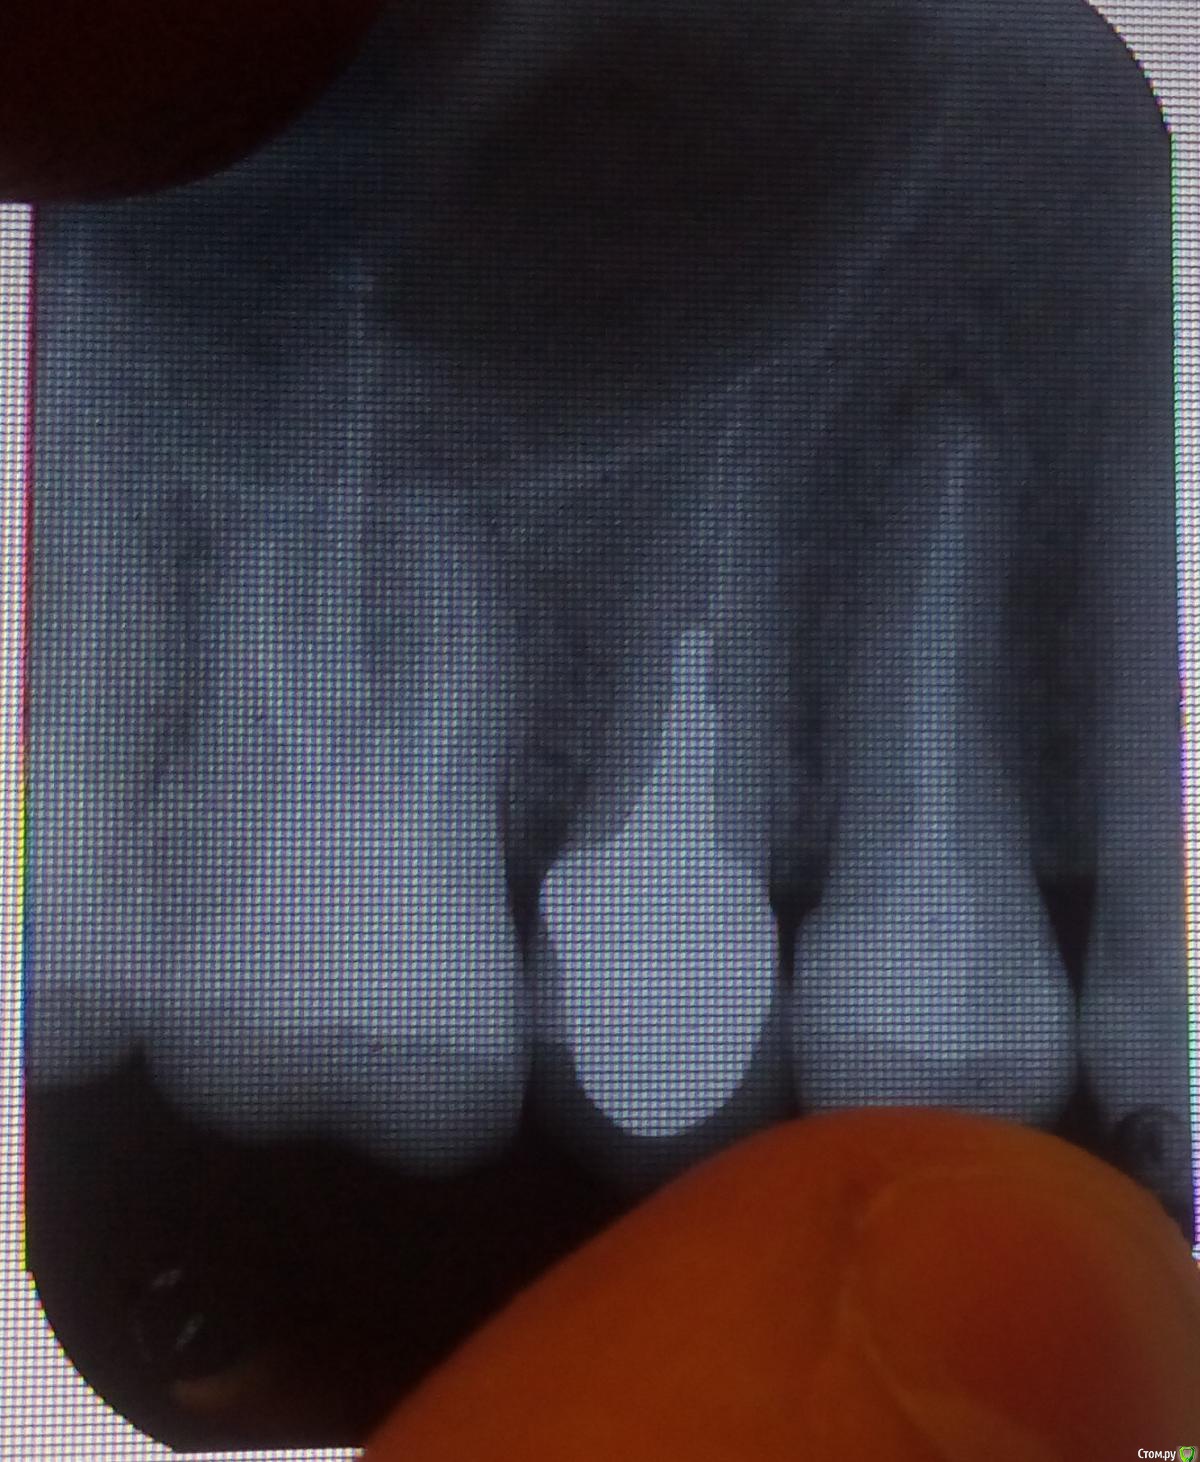

Bill_Lance Опубликовано 20 апреля, 2017 Автор Поделиться Опубликовано 20 апреля, 2017 (изменено) Появился еще один рентген. Проблемный зуб на снимке - самый правый полностью видный. Под корнем видна небольшая темная область. http://i89.fastpic.ru/big/2017/0421/a0/fd4bdcff62fc845f92e7786362e58aa0.jpg Изменено 20 апреля, 2017 пользователем Bill_Lance Ссылка на комментарий